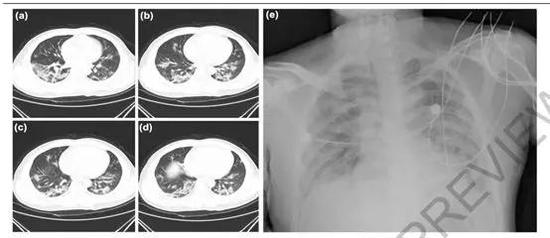

其于2019年12月26日在武汉一家医院住院,表现出呼吸系统疾病症状,包括发烧、胸闷和咳嗽。联合使用抗生素、抗病毒药和糖皮质激素进行治疗,但患者表现出呼吸衰竭,治疗三天后病情无改善。

该例病人发病6天后,左肺可见明显病灶。

石正丽团队的研究分析了7例重症肺炎患者的样本,其中6人为武汉海鲜市场内的工人。论文指出,临床医生最早根据临床症状及体温升高、淋巴细胞、白细胞减少(有时为正常)、胸片新发肺部浸润、抗生素治疗3天后无明显改善等标准,将这些患者确定为病毒性肺炎。